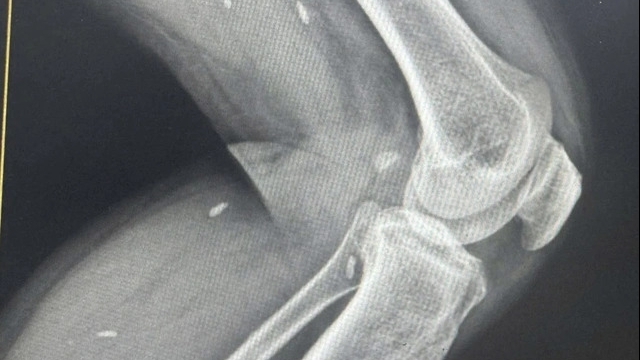

![]() |

| Một bệnh nhân ngộ độc Botulinum |